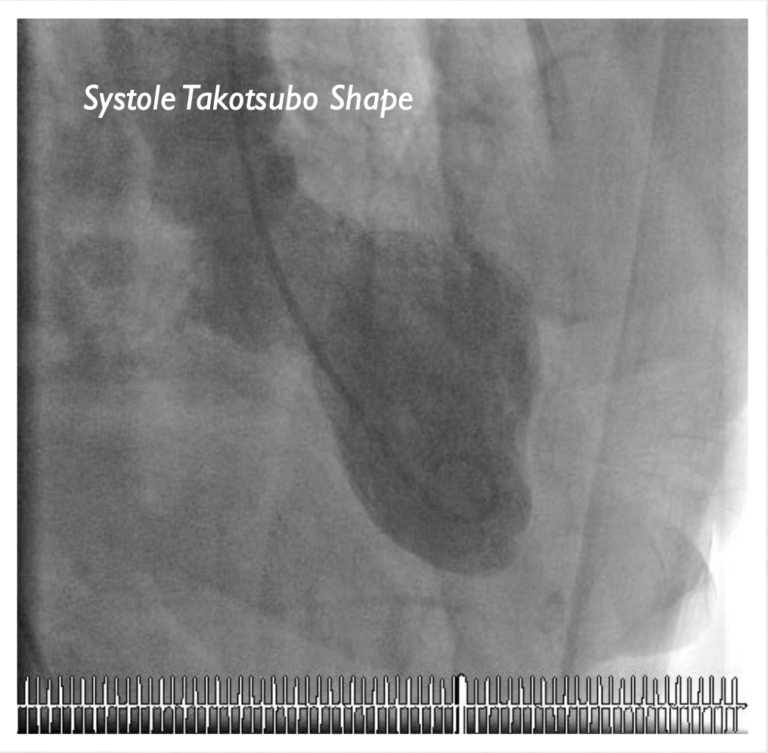

要区分心碎综合征和心脏病发作(心肌梗塞),就需要在急性发作期进行冠状动脉造影和左心室造影(左心室衬度成像)。由于左心室的成像与历史上日本人用来捕捉章鱼、一类带有细颈和球根状的砂锅十分相似,因此用“章鱼壶”一词来描述。心碎综合征与典型心脏病发作之间的最大区别是,前者在冠状动脉造影时没有发现冠状动脉阻塞。